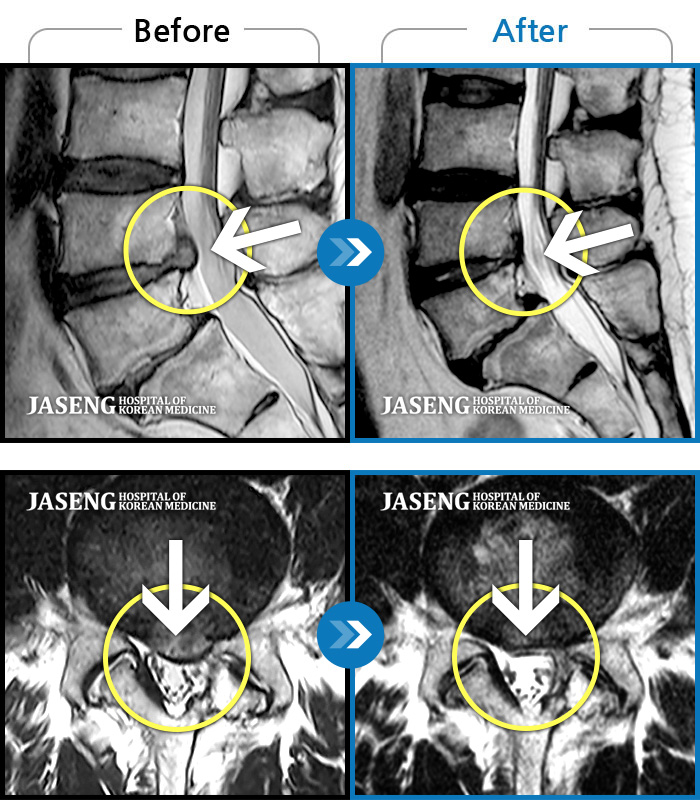

허리디스크

강남 · 이진호 원장

좌측 골반통증으로 보행 시 다리를 뻗을 수가 없고 극심한 요통 및 종아리 통증으로 자세변경을 바로 할 수가 없는 상태

촬영시기

2021.10.20 ~ 2022.12.14

2022.12.23